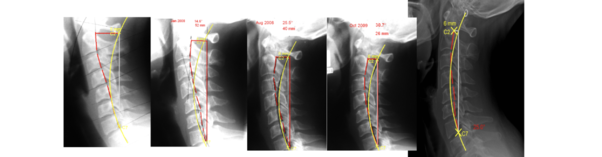

Dr. Emilie's Spine Makeover

“I had been seeing a chiropractor since I was a child - mostly for wellness!

My mom knew it was good to take care of my spine and I liked going.. However, I didn't have xrays done until I was 14 (see first xray). The chiropractor explained my spine was going the wrong way.

Unfortunately, despite getting adjusted, we never did anything specific to correct the shape of my spine. By then I had developed headaches, neck pain, back pain, even seasonal allergies. When I got adjusted it helped me feel better, but my problems always came back.

Many years later I had a corrective care chiropractor take xrays. By then my spine looked worse and he started to help correct the actual shape of my spine. Now I no longer have the same pains, I am more mobile, healthy and able to be well!

This is why I'm passionate about helping others get to the SOURCE of their problem and CORRECT it!”

-Dr. Emilie.